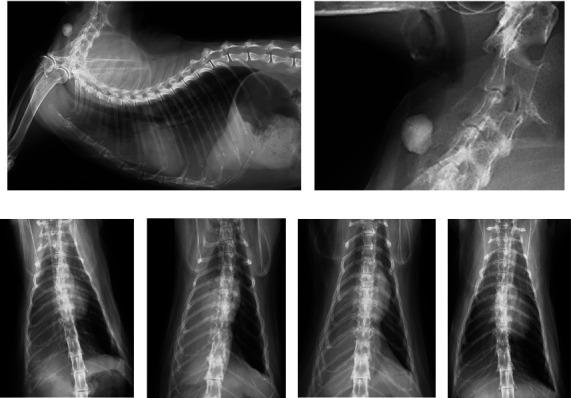

There have been few reports of emergency cases of proximal tracheal foreign bodies in dogs and cats. Here, we report a dog and a cat that underwent an emergency tracheotomy for a foreign body in the proximal trachea. Case 1 was a dog with respiratory arrest caused by a large stone in the proximal trachea. The stone was immediately removed via tracheotomy without anesthesia. After intubation and ventilation under anesthesia, hypoxia persisted but improved after aspiration of 100 mL of bloody fluid from the lower trachea. Case 2 was a cat with dyspnea because of a proximal tracheal stone and increased radiopacity in the right lung. The stone was removed via tracheotomy after mask induction of anesthesia, followed by intubation and incision closure. Radiographs immediately after extubation showed worsened right lung atelectasis, alleviated by reintubation and positive pressure ventilation. Both patients recovered completely after surgery. An emergency tracheotomy may be indicated for a large foreign body in the proximal trachea. Additionally, concurrent conditions in the lower respiratory tract should be addressed.

关于犬猫近端气管异物急诊病例的报道较少。在此,我们报告一只犬和一只猫因近端气管异物接受了紧急气管切开术。病例1是一只犬,因近端气管内的一块大石头导致呼吸骤停。在未麻醉的情况下通过气管切开术立即取出了石头。麻醉下插管和通气后,仍存在低氧血症,但从下呼吸道吸出100毫升血性液体后有所改善。病例2是一只猫,因近端气管结石和右肺不透光性增加而出现呼吸困难。在面罩诱导麻醉后通过气管切开术取出结石,随后进行插管和切口闭合。拔管后立即进行的X线片显示右肺肺不张加重,通过再次插管和正压通气得到缓解。两名患者术后均完全康复。对于近端气管内的大异物,可能需要进行紧急气管切开术。此外,应处理下呼吸道的并发情况。